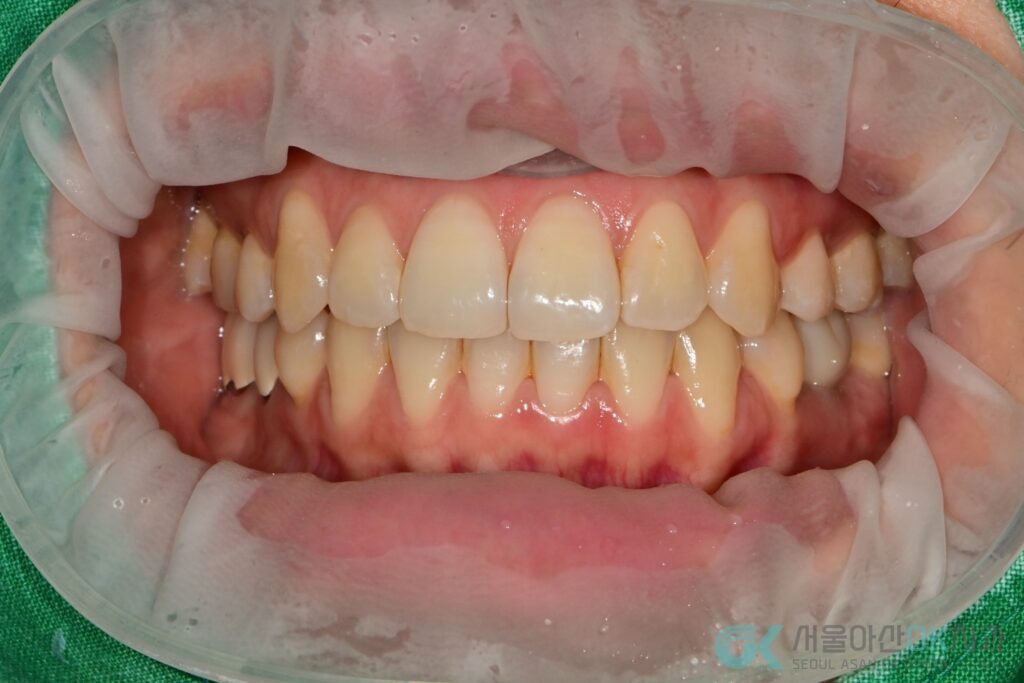

6) 최종 단계: 나사 유지형 지르코니아 보철(SCRP) 장착

2025-08-09 #36 SCRP 타입(나사로 고정하는 보철) 장착을 시행했고,

스크류 타이트닝(기록상 30N) 교합 조정 홀 임시 충전 후,

2025-08-16에 레진으로 최종 홀 충전까지 마무리했습니다.